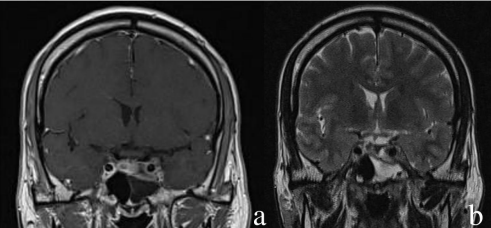

Figure 1: a- coronal T1 + contrast MRI showing a pituitary adenoma invading the left cavernous sinus with a heterogeneous enhancement- coronal T2 showing a CSF collection in the left sphenoid sinus.

The MRI showed a good response for treatment with a partial reduction of the tumoral size, however, the left sphenoid sinus was filled by CSF-like intensity collection (figure1). The skull base CT showed a bony defect (erosion) of the sella extending to the tuberculum. We have confirmed this osteodural defect using a brain isotopic transit study that confirmed the same findings.